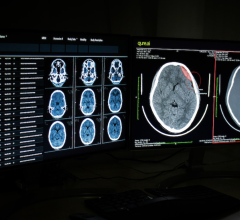

October 2, 2020 — The Galan 3T and Orian 1.5T magnetic resonance imaging (MRI) platforms, both with Advanced intelligent ...

October 1, 2020 — Canon Medical’s Aquilion ONE / PRISM Edition, designed for deep intelligence, integrates artificial ...

September 30, 2020 — A new artificial intelligence (AI) algorithm can identify when medical images are likely to be ...